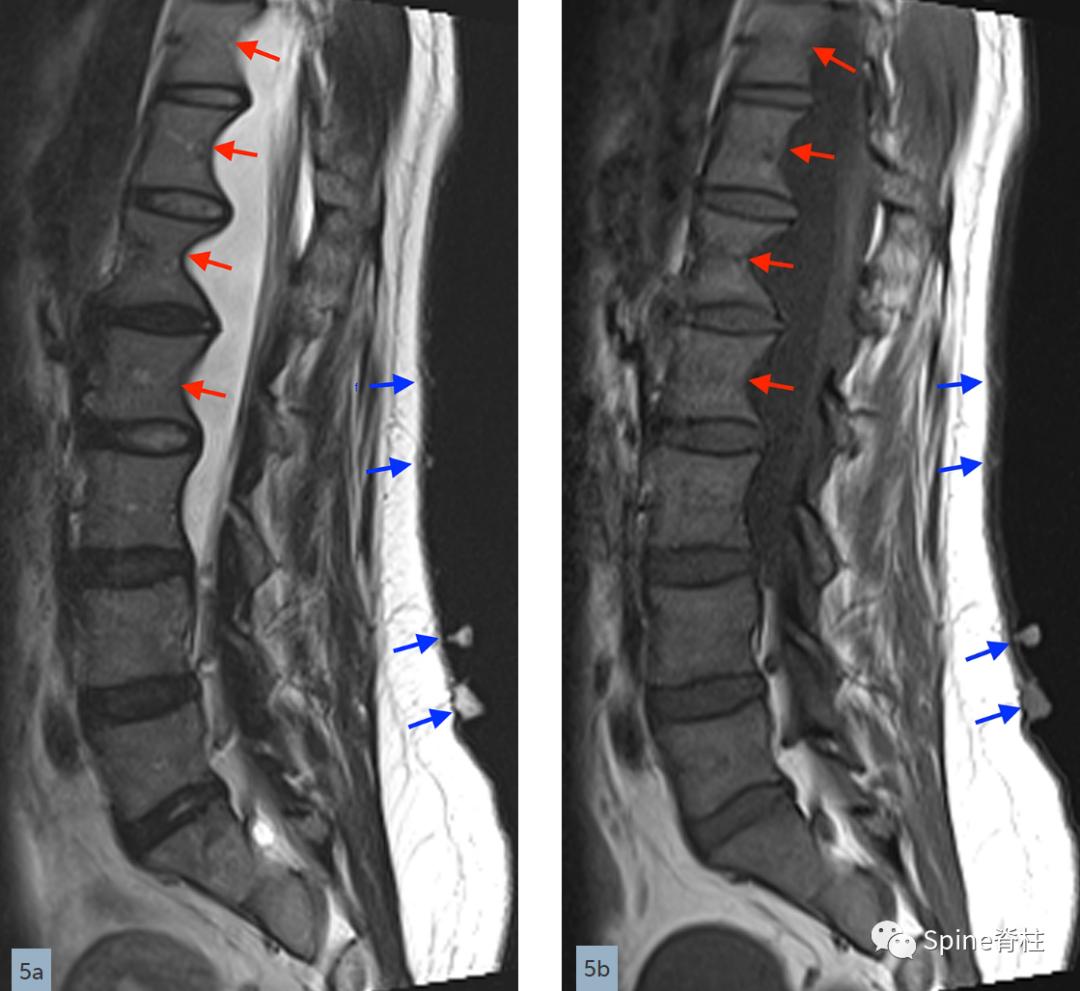

除了马凡综合征,硬膜扩张也是 1 型神经纤维瘤病的一种表现,在颅骨和脊柱均可发生。在脊柱中,由于胸部和蛛网膜下腔之间的压力差以及椎体后部的扇形凹陷或骨缺损,硬膜囊侧和前膨出通常发生在胸椎。硬膜囊膨出(Meningocele)通常与胸椎侧凸相关(下图)。其他发现包括椎体楔形变、椎弓根侵蚀、椎间孔扩大和脊柱后凸。1型神经纤维瘤病的骶骨病变通常是由于神经纤维瘤的直接累及或硬膜扩张伴椎间孔扩大引起的重塑。

矢状位T2(a)和T1(b)加权像提示下胸椎和上腰椎硬膜扩张伴显著的椎体后壁扇形凹陷(红色箭头)。轴位T2(c)和T1(d)加权像提示硬膜囊外侧膨出(绿色箭头)伴椎体扇形缺损。蓝色箭头是指继发于皮肤神经纤维瘤的多发性皮肤结节